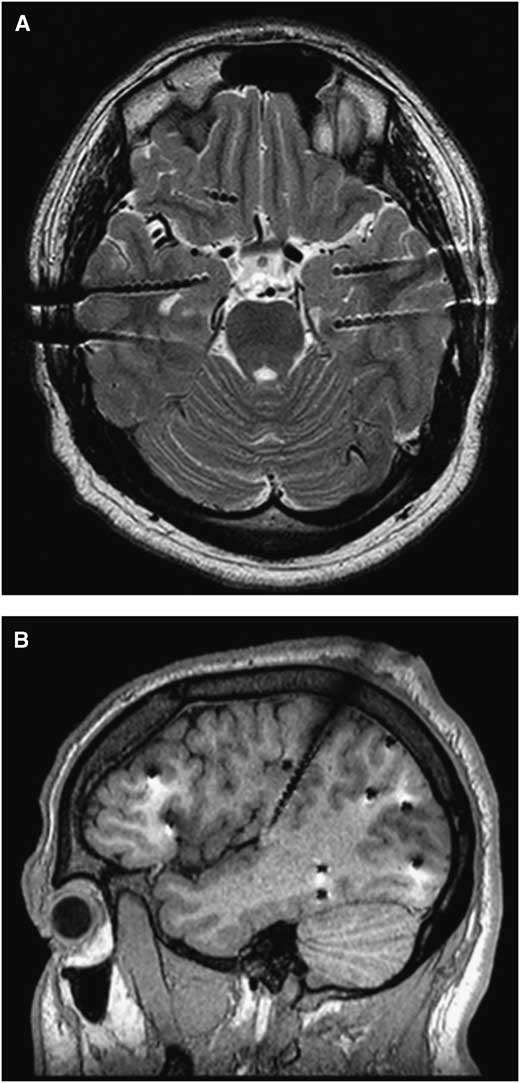

A typical T2-weighted axial image is shown in Figure 1A. When seen along its plane, the electrode and each electrode contact are well-visualized. Figure 1B shows a sagittal T1-weighted image demonstrating the degree of metallic artifact. The actual diameter of the electrode is 0.8 mm.

Figure 1 (A) An axial T2 section from an SEEG study for bitemporal epilepsy. When seen along its plane, the electrode and each electrode contact are well-visualized. (B) A sagittal T1 section from an SEEG study for frontal and posterior quadrant epilepsy. Electrodes were aimed at the orbitofrontal, temporal, and occipital areas from a lateral approach and the insula from a superior approach. A metallic artifact (appeared larger than the electrode diameter, 0.8 mm) is appreciated.